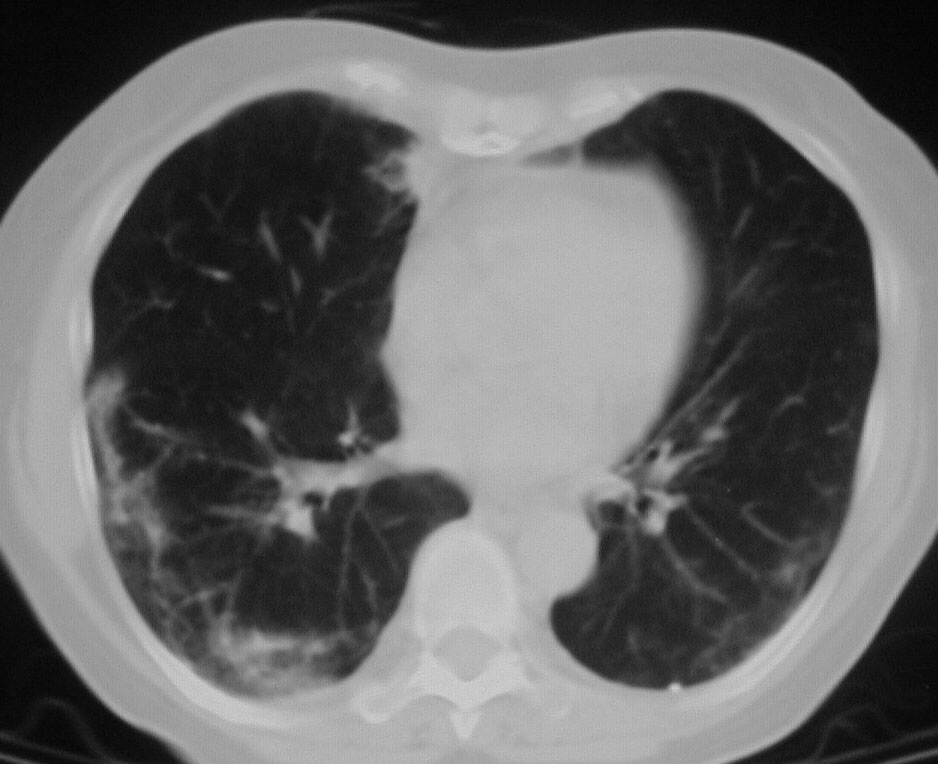

SIGNO DE LAS ALAS DE MARIPOSA INVERTIDAS

La presencia de infiltrados alveolares de disposición periférica y bilateral, respetando las regiones perihiliares, provoca una imagen opuesta a la del signo de las alas de mariposa. Este hallazgo se ve en la neumonía eosinófica.

La imagen de la TC muestra los focos de condensación alveolar periféricos y bilaterales, con predominio en el pulmón derecho.